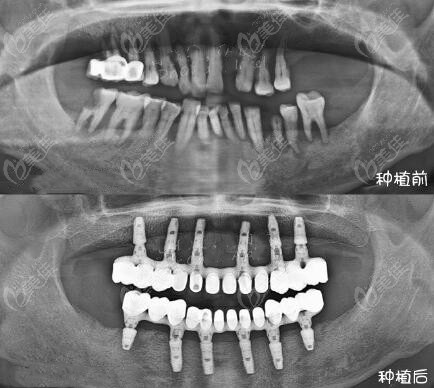

2、2025合肥种植牙医生推荐:袁宇

坐诊医院:安徽合肥贝杰口腔

种牙擅长:吸附性活动假牙种植、微创美学修复种植、不痛拔牙、

治疗经验:袁宇拔牙5000余例、单颗种植牙千余例;

医生简介资料:袁宇从事种植工作10余年,现任合肥贝杰口腔(政务院)种植院长。

▼袁宇医生完成的单颗种植牙病例图▼

2025合肥种植牙医生推荐:袁宇